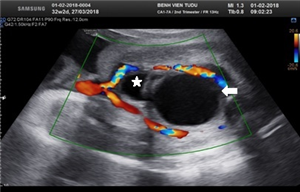

Giới thiệu Case 405: Maternal and infatile choriocarcinoma, Dr Phan Thanh Hai, Medic medical Center HCMC